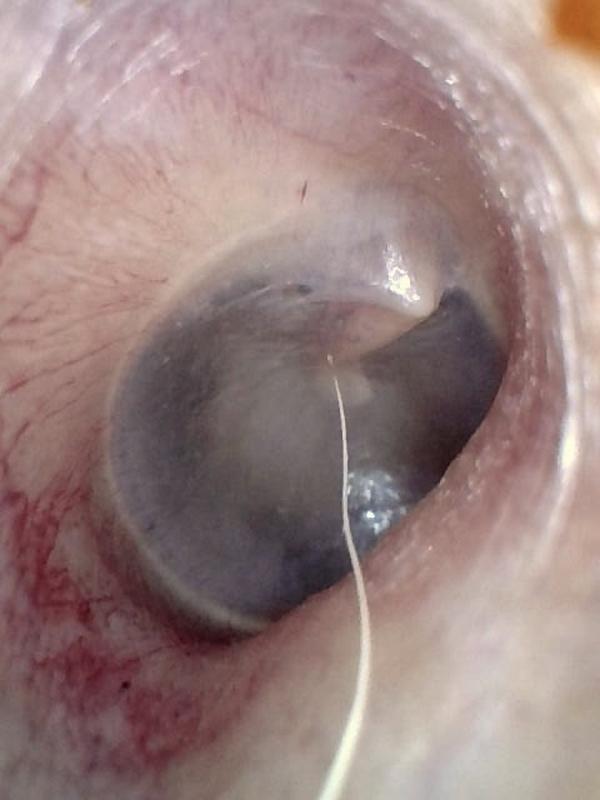

Middle Ear Effusion